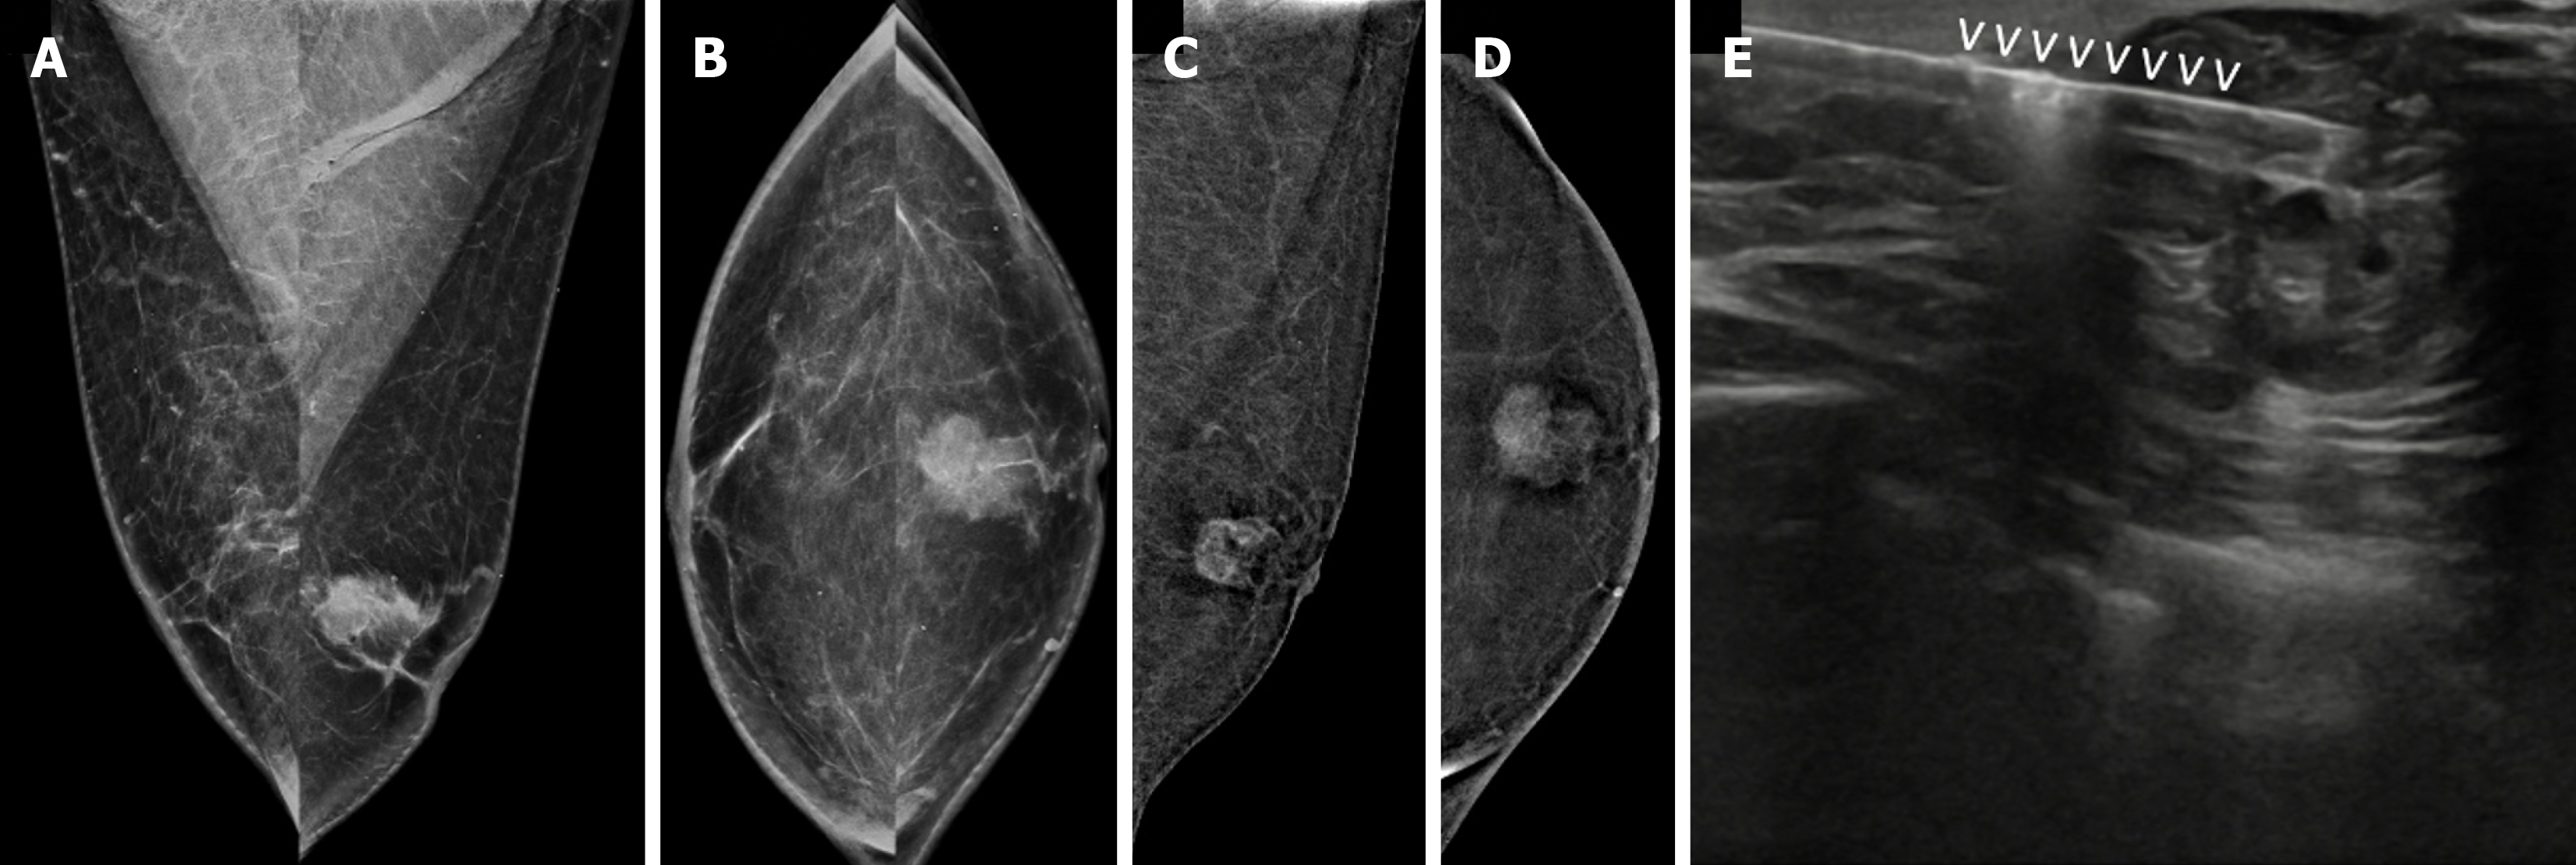

Figure 18  Ductal carcinoma in situ in a 69-year-old male with a palpable lump in the left breast.

A: Mediolateral oblique (MLO) view; B: Cra

Figure 19  Invasive breast cancer in a 74-year-old male with a hard lump in left breast.

A: Mediolateral oblique (MLO) view; B: Craniocaudal (CC) view showing an irregular, high-density mass; C and D: Contrast-enhanced mammography; C: MLO and D: CC views of the recombined images showing heterogeneous enhancement; E: Ultrasound; F: Elastography images showing an irregular heteroechoic mass with microlobulated margins that appear hard on elastography; G-J: Magnetic resonance images showing an irregular mass; G: T1-weighted image showing a hypointense signal; H: T2-weighted image showing a heterogeneously hyperintense signal; I and J: DWI-ADC images showing central diffusion restriction; K: Postcontrast image showing heterogeneous septal enhancement; L: Histopathological examination image (hematoxylin–eosin, × 40) showing invasive breast cancer (no special type) composed of tumor cells arranged in clusters and tubules.